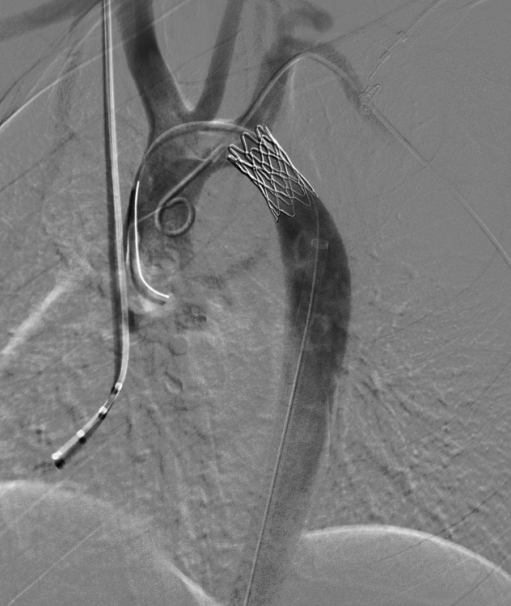

按照治疗计划,王景峰教授、聂如琼教授、林永青副教授等手术团队主要成员反复讨论、确定手术具体细节,顺利地为小丽进行了手术。术中造影证实小丽降主动脉起始段局部狭窄,仅剩余约7mm的直径,狭窄上下压力差值达到了53mmHg。术中准确定位植入一枚14×28mm的覆膜支架。术后复查狭窄上下压力差值下降到3mmHg,小丽原本没有搏动的下肢动脉重新跳动了起来。

术中植入一枚覆膜支架。